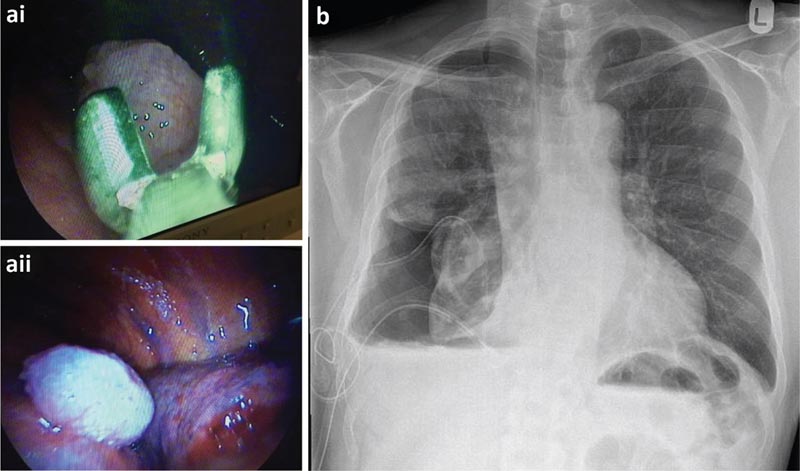

La cytologie du liquide pleural n’étant pas diagnostique, le patient a subi une thoracoscopie sous anesthésie locale et sédation modérée (TAS), également appelée thoracoscopie médicale ou pleuroscopie. Il s’agit d’une procédure médicale réalisée par des pneumologues, qui comprend un examen interne, une biopsie et/ou l’administration d’agents thérapeutiques dans la cavité pleurale.

Le patient a subi une TAS qui a montré un grand nombre de nodules au niveau des plèvres viscérales et pariétales. Il a été décidé d’insérer un cathéter pleural à demeure (CPP) au moment de la thoracoscopie pour un poumon probablement non expansible.

a) Biopsies de la plèvre pariétale réalisées lors d’une thoracoscopie et vue thoracoscopique d’un nodule malin. b) Radiographie pulmonaire post-thoracoscopique.

Les biopsies pleurales ont révélé un mésothéliome épithélioïde malin. Après discussion en équipe multidisciplinaire, le patient a été orienté vers l’oncologie pour un traitement. Le patient a continué à drainer son IPC 3 fois/semaine et a ensuite réalisé une autopleurodèse. Le RPC a été supprimé peu de temps après.